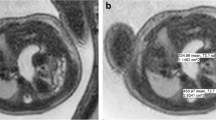

Images were evaluated by two investigators in concert: one fellowship-trained, board-certified radiologist (D.M.T.) with more than 25 years of experience in obstetrics imaging including antenatal ultrasound and fetal MRI and one fellowship-trained, board-certified radiologist (A.A.B.) with 5 years of experience in fetal MRI. All measurements were obtained on Philips IntelliSpace PACS Radiology version 4.4 workstations (Philips Healthcare, Brisbane, CA). Measurements obtained from MR images included actual observed lung volume, intrathoracic liver volume and herniated organ volume. The diaphragm location was estimated at the level of the defect to obtain these volumes (Fig. 1). Volumes of the visualized lung parenchyma (Fig. 2), herniated organs (Fig. 2) and intrathoracic liver (Fig. 3) were obtained by drawing a region of interest (ROI) measurement around the area of interest (i.e. visualized lung parenchyma, herniated organs or intrathoracic liver) for each slice, adding the ROI measurements, and then multiplying the summed measurements by the slice thickness. Mediastinum was excluded from the volume measurements. Visualized lung parenchyma (observed total lung volume [TLV]) was defined as the volume of lung parenchyma present. Herniated organ volume (mass) was defined as the volume of herniated contents in the thoracic cavity (e.g., stomach and bowel). Intrathoracic liver volume (liver up) was defined as the volume of liver present within the thoracic cavity. ROI measurements were completed in the coronal plane. The total thoracic cavity volume, not including the mediastinum, was the summation of observed TLV, volume of herniated liver, and volume of herniated organs, referred to as the predicted TLV. This was preferred over nomograms of expected TLV because of the large variability of fetal weights and, therefore, lung volume measurements. The measurements were then used to calculate the percentage of the thoracic cavity occupied by lung (observed to predicted TLV) and the percentage of thoracic cavity occupied by liver (% of thorax occupied by liver).

Region of interest (ROI) measurements of the intrathoracic liver. a–c Coronal T2-W short tau inversion recovery (a), breath-hold T1 gradient recalled echo (b) and balanced steady-state free precession (c) images obtained at 27 weeks’ gestation through the fetal thorax demonstrate left congenital diaphragmatic hernia with the intrathoracic liver. The dotted line indicates ROI of residual lung, the dashed line indicates ROI of mediastinum and the solid line indicates ROI of liver